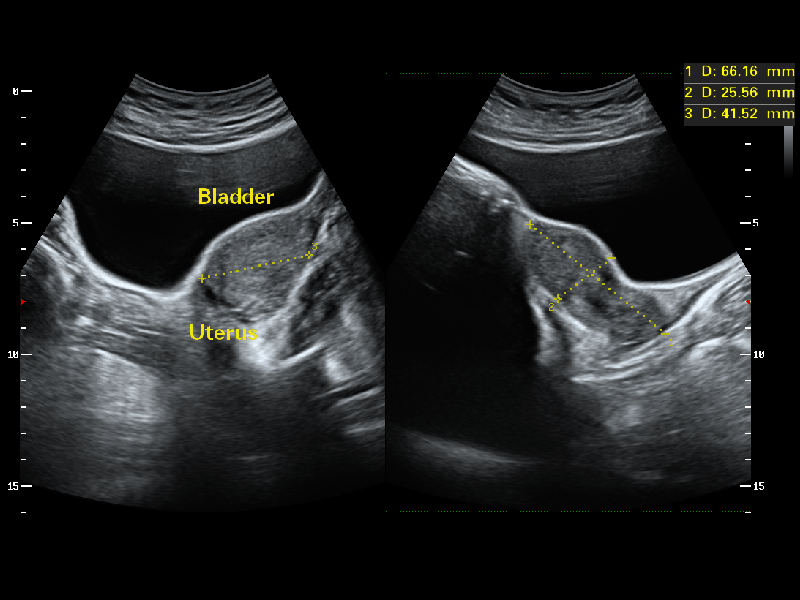

High Efficiency of follicle analysis is achieved by AVC Follicle, a Volume-data based automatic follicular calculation including the number and volume. Follicles are sorted by sizes in the results and rendered in different colors with numbers for better Visualization.

1Mhz Low Frequency Convex transducer greatly improve the Piezoelectric crystal signal ratio, Acquire stunning Quality Images & New Generation μ-Scan + Provide High sensitivity & High Resolution for the Both near and far field, 200 degree Transvaginal Probe provides extraordinary image quality for gynaecology, Early Obstetrics scan, HD Linear Transducer achieve a Uniform image Quality, high sensitive acoustic spectrum in vascular, brest, MSK, Thyriod, Lower and upper limp, Etc and Aeroscan CD40 enhancing boundary improved visualization in 2D and Color Doppler in Echocardiogram with all premium Features loaded., CD40 Supports Ultras-wide Frequency bandwith Probes - Intra-operative, Paediatric, Neonatal, TEE, Transrectal, Volume Transducer & More.,